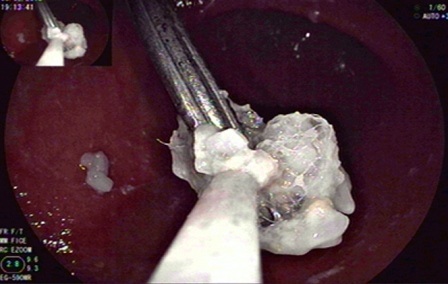

Nhóm y bác sĩ thủ thuật đã quyết định sử dụng rọ chuyên dụng Roth Net để gắp thành công đinh sắt ra khỏi dạ dày cháu bé. Kết quả đã không gây tổn thương cho dạ dày, thực quản cháu Q.. Hiện sức khỏa cháu đã tiến triển tốt.